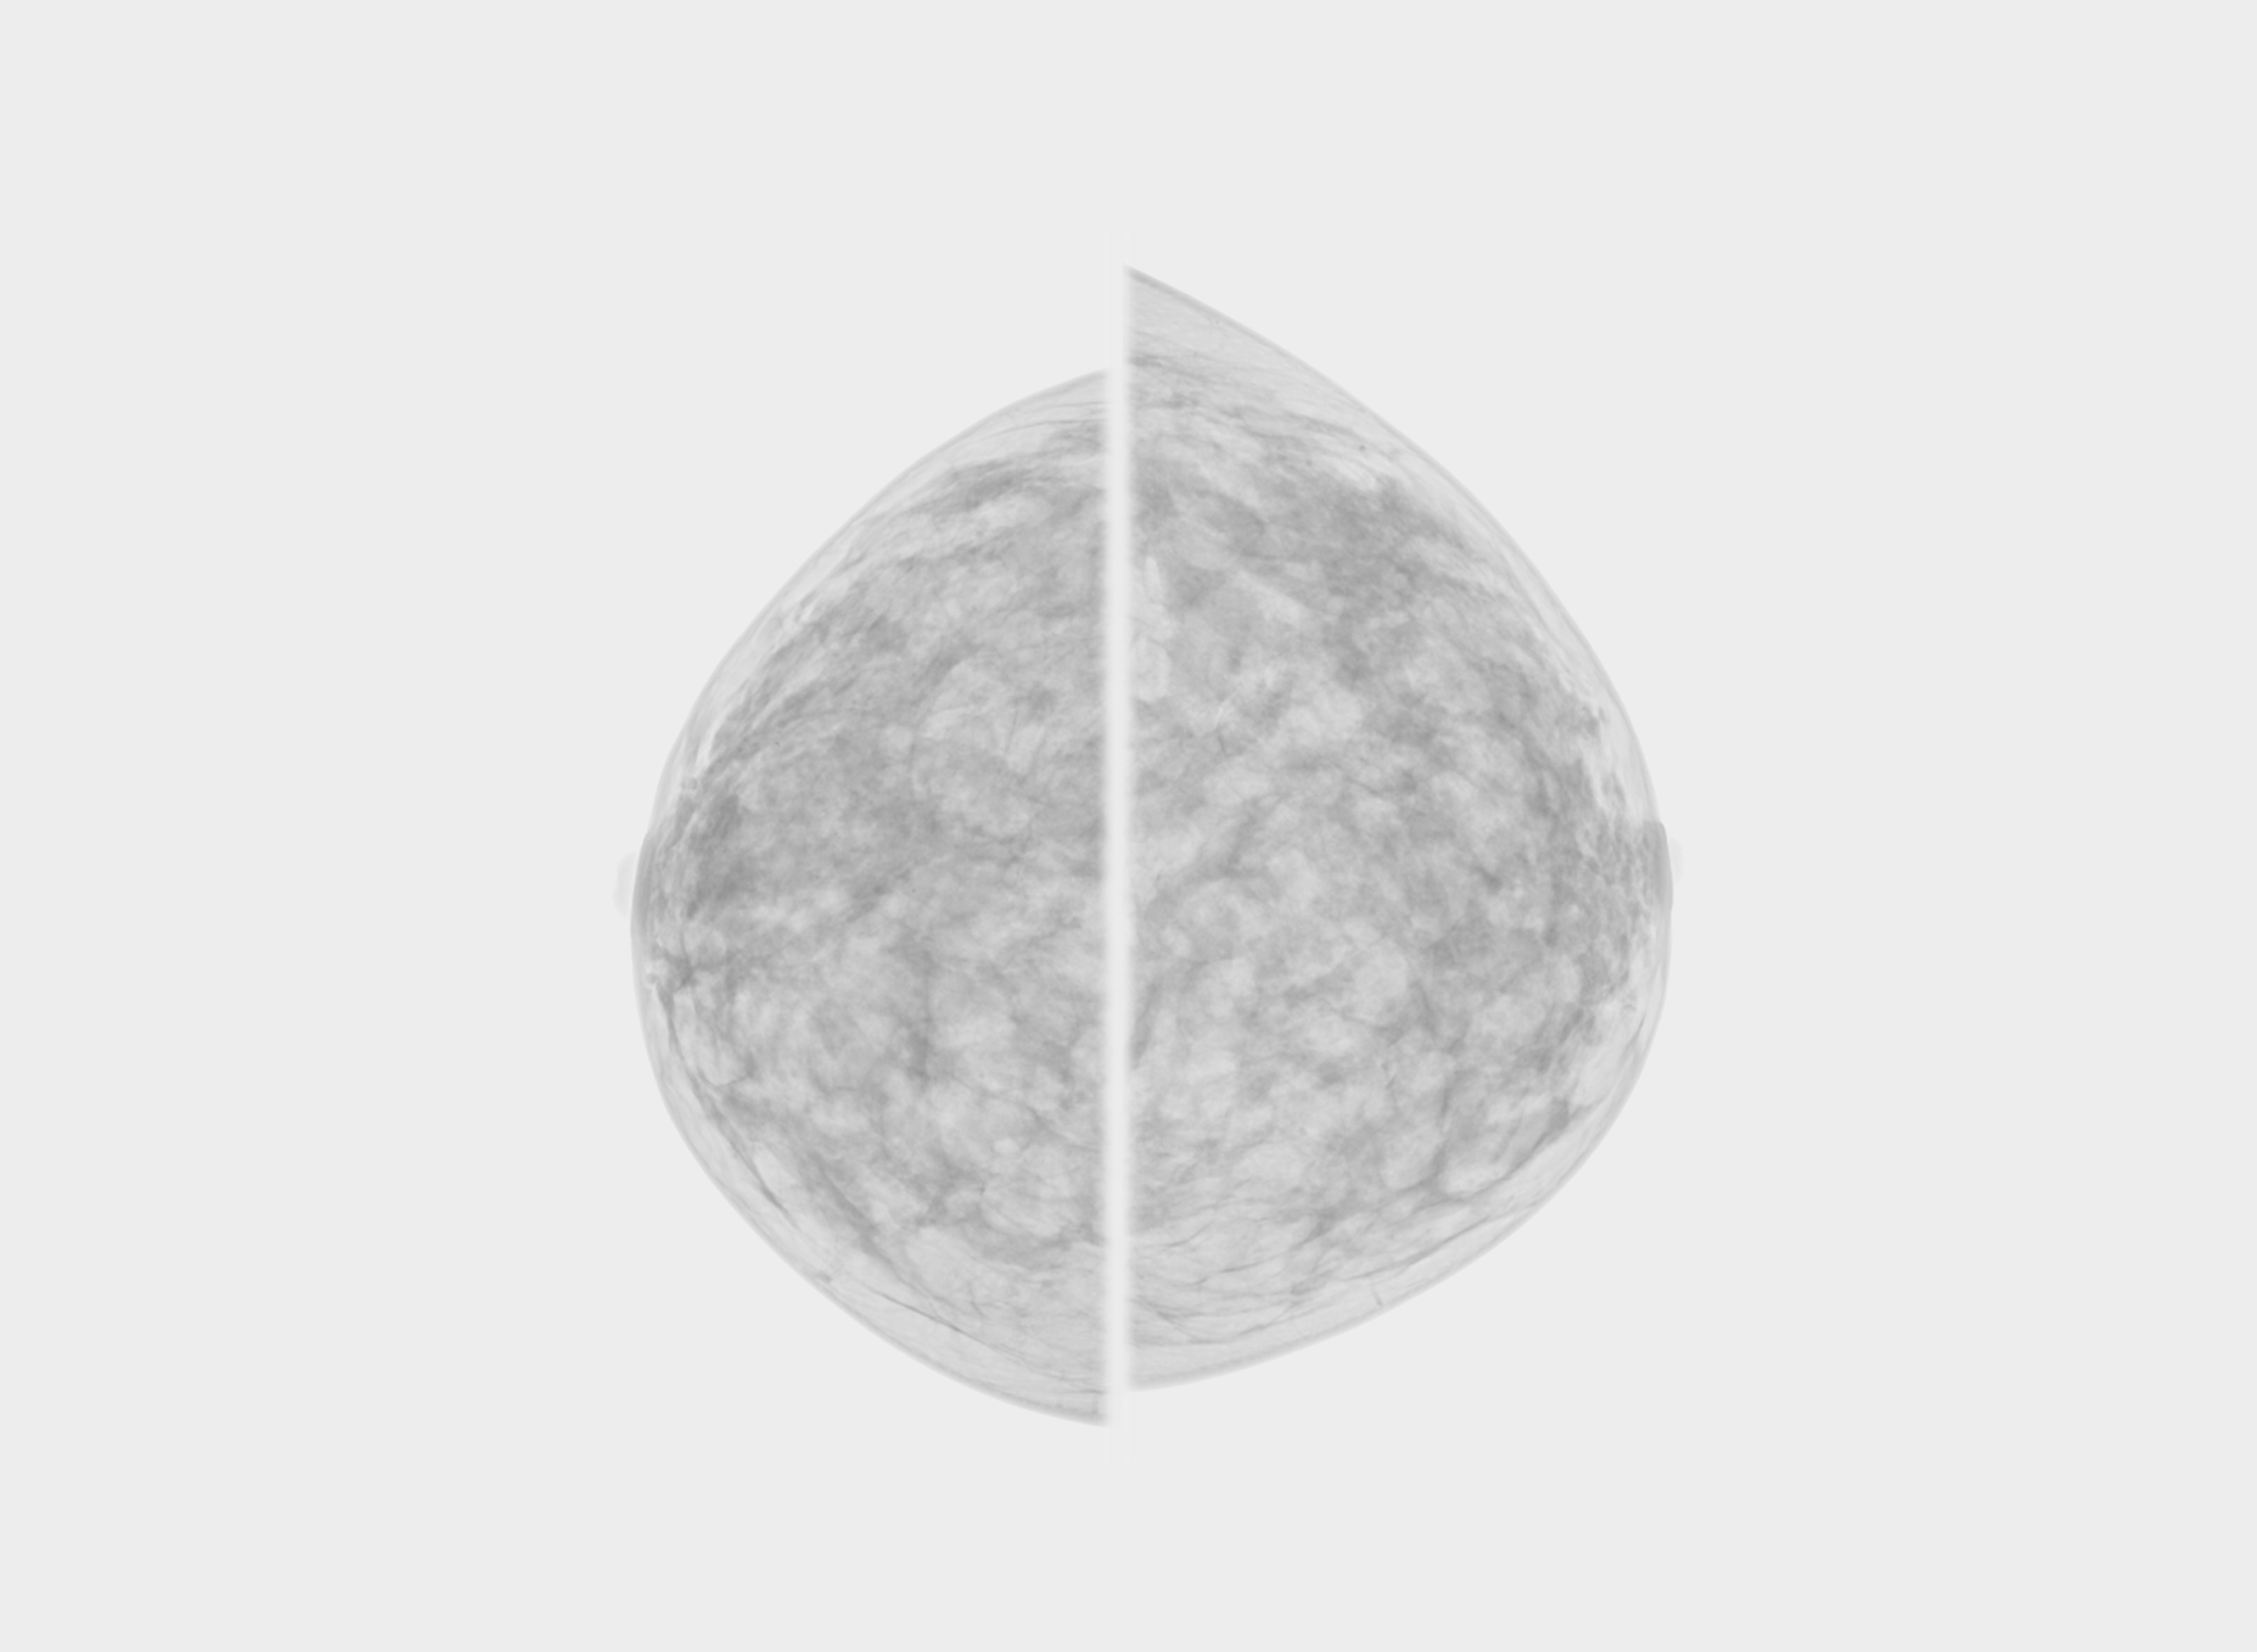

See how Carebot works in practice. Compare the image with AI and without AI.

Without Carebot

With Carebot